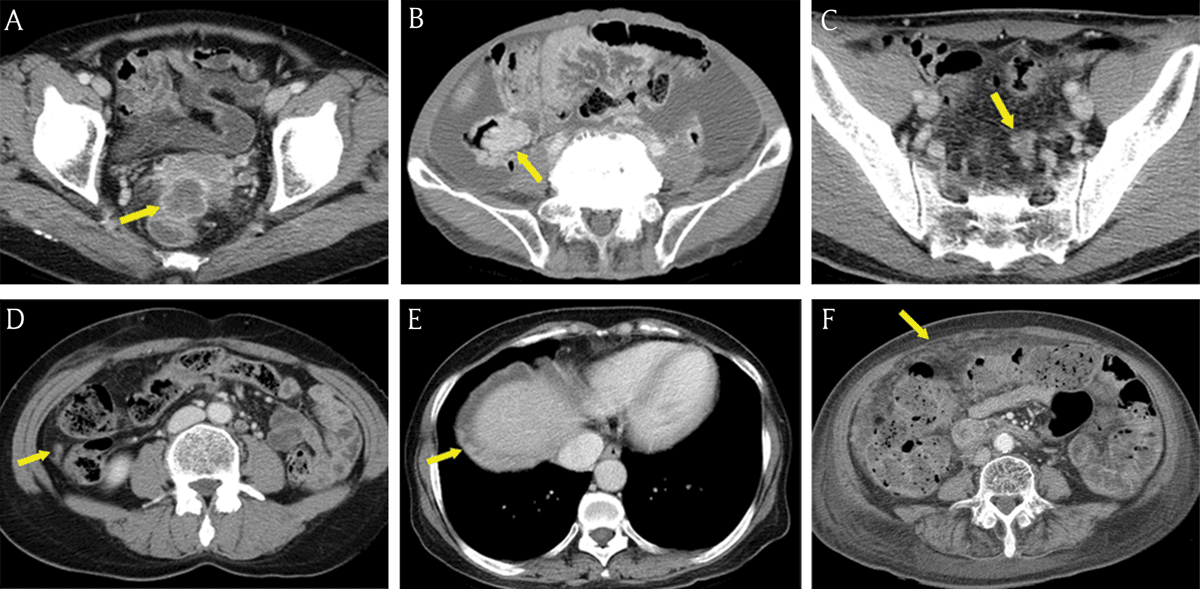

Figure 3

Common seeding sites in peritoneal carcinomatosis. (A–E) Axial portal venous phase CT images show the frequent locations for peritoneal seeding (arrows): peritoneal reflexion (A), lower small bowel mesentery (B), sigmoid mesocolon (C), right paracolic gutter (D), right subphrenic space (E), and greater omentum (F).